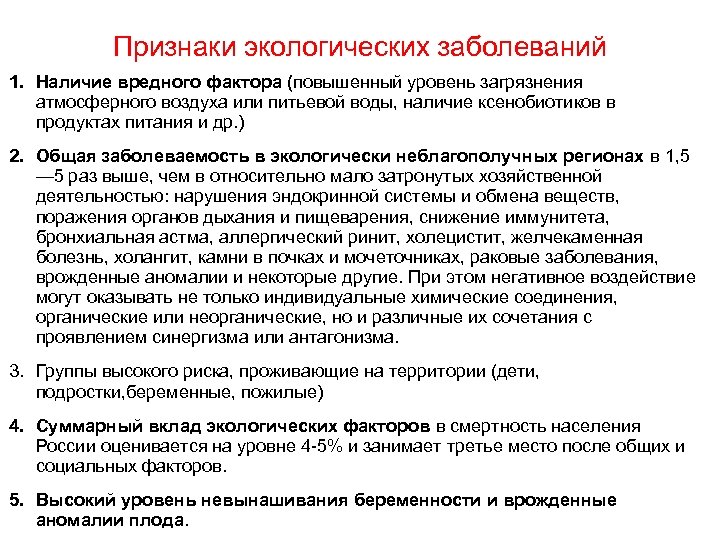

Признаки экологических заболеваний 1. Наличие вредного фактора (повышенный уровень загрязнения атмосферного воздуха или питьевой воды, наличие ксенобиотиков в продуктах питания и др. ) 2. Общая заболеваемость в экологически неблагополучных регионах в 1, 5 — 5 раз выше, чем в относительно мало затронутых хозяйственной деятельностью: нарушения эндокринной системы и обмена веществ, поражения органов дыхания и пищеварения, снижение иммунитета, бронхиальная астма, аллергический ринит, холецистит, желчекаменная болезнь, холангит, камни в почках и мочеточниках, раковые заболевания, врожденные аномалии и некоторые другие. При этом негативное воздействие могут оказывать не только индивидуальные химические соединения, органические или неорганические, но и различные их сочетания с проявлением синергизма или антагонизма. 3. Группы высокого риска, проживающие на территории (дети, подростки, беременные, пожилые) 4. Суммарный вклад экологических факторов в смертность населения России оценивается на уровне 4 5% и занимает третье место после общих и социальных факторов. 5. Высокий уровень невынашивания беременности и врожденные аномалии плода.

Признаки экологических заболеваний 1. Наличие вредного фактора (повышенный уровень загрязнения атмосферного воздуха или питьевой воды, наличие ксенобиотиков в продуктах питания и др. ) 2. Общая заболеваемость в экологически неблагополучных регионах в 1, 5 — 5 раз выше, чем в относительно мало затронутых хозяйственной деятельностью: нарушения эндокринной системы и обмена веществ, поражения органов дыхания и пищеварения, снижение иммунитета, бронхиальная астма, аллергический ринит, холецистит, желчекаменная болезнь, холангит, камни в почках и мочеточниках, раковые заболевания, врожденные аномалии и некоторые другие. При этом негативное воздействие могут оказывать не только индивидуальные химические соединения, органические или неорганические, но и различные их сочетания с проявлением синергизма или антагонизма. 3. Группы высокого риска, проживающие на территории (дети, подростки, беременные, пожилые) 4. Суммарный вклад экологических факторов в смертность населения России оценивается на уровне 4 5% и занимает третье место после общих и социальных факторов. 5. Высокий уровень невынашивания беременности и врожденные аномалии плода.